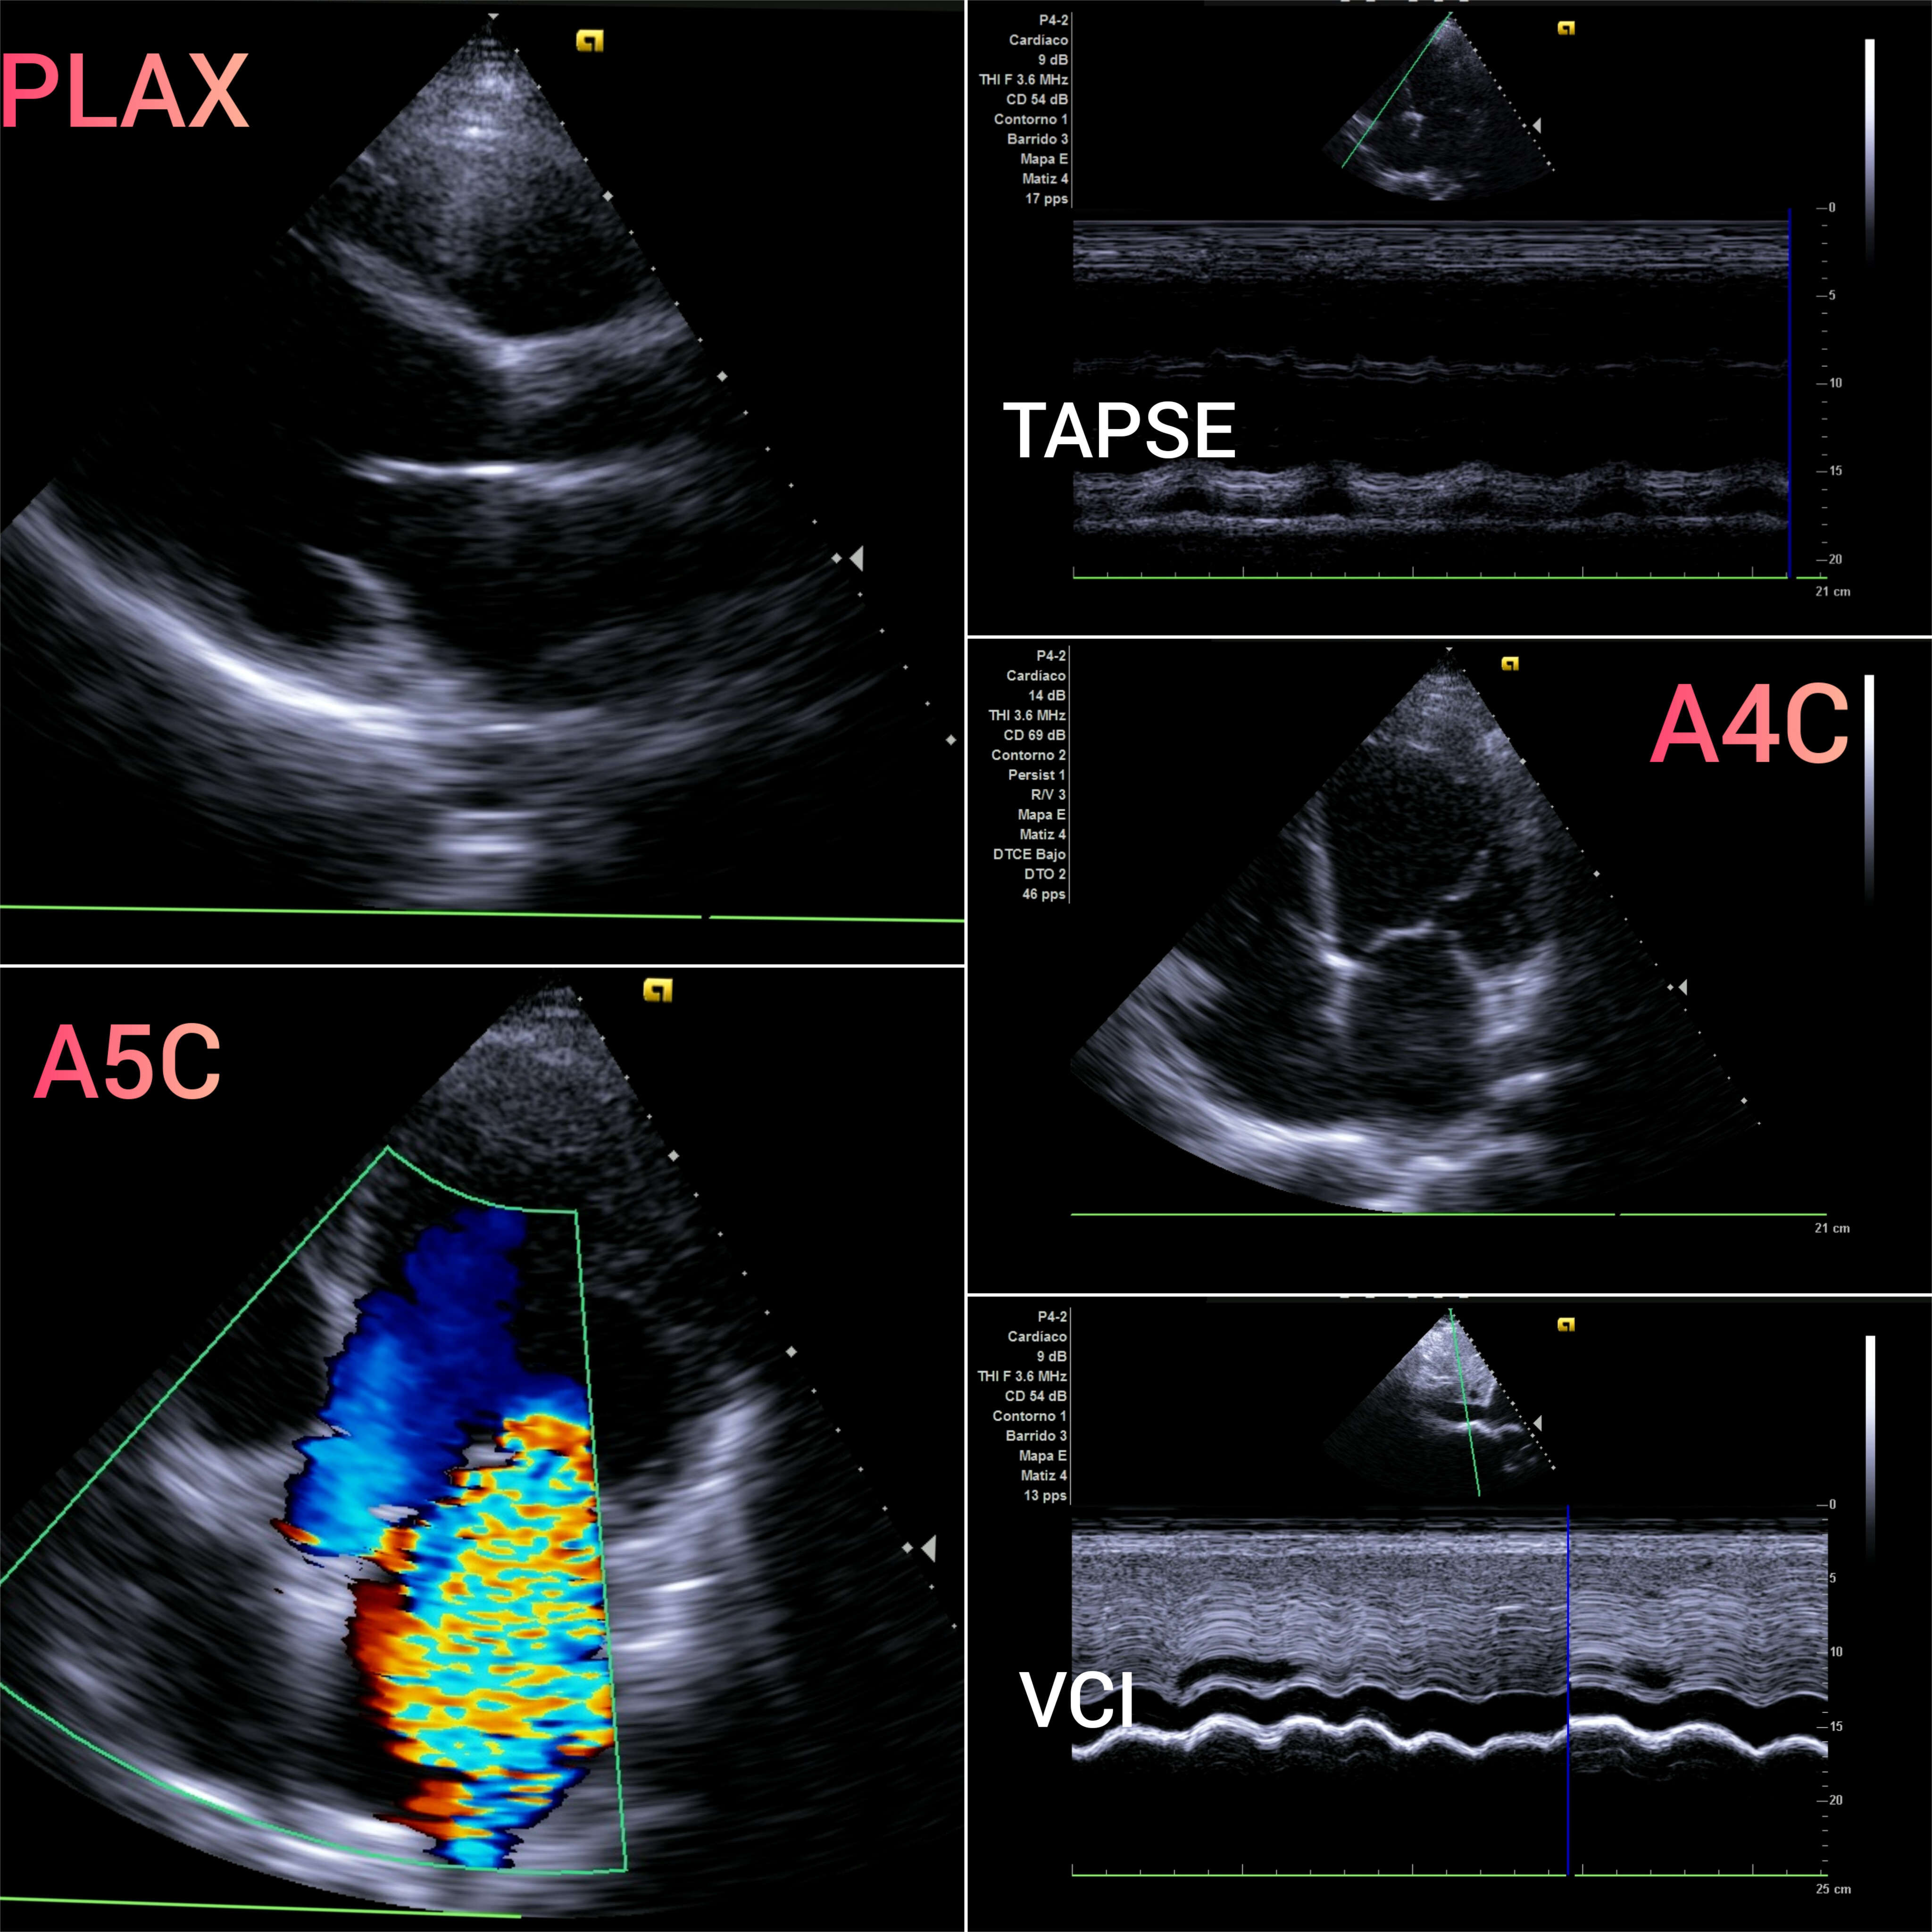

VEXUS: Vena cava inferior VCI 2,1 con colapsabilidad > 50%; Flujo portal y renal continuo.

EcoCardioscopia: Mejoría de contractilidad subjetivamente respecto a previo, cavidades izquierdas dilatatadas tanto VI como AI.

Desde Medicina de Familia, debemos ser proactivos en la detección y control de la IC y sus factores predisponentes. La ecocardioscopia y VEXUS en consulta complementa a ECG, Radiografía y analítica con ProBNP y CEA125. Finalmente, la longitudinalidad en Medicina de Familia nos permite tener presente los antecedentes personales así como los familiares.